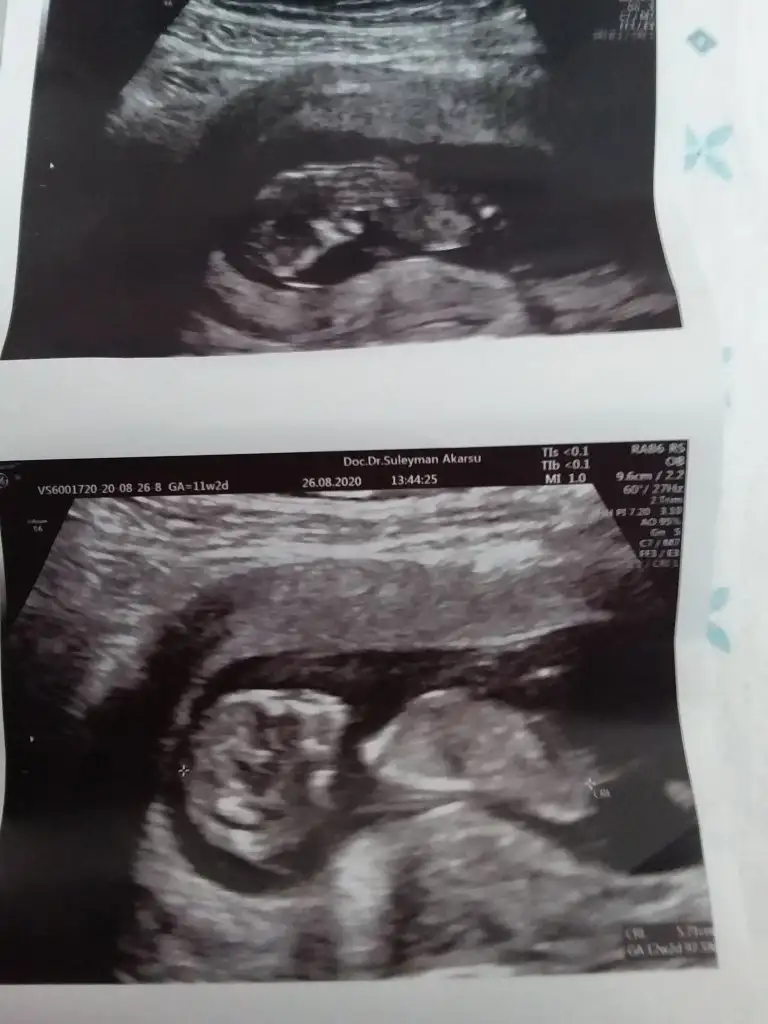

Erkek gibi sanki 13 hafta olursa tekrar paylaşın net değil USG emin olamadimMerhaba 11+6 günlük bebeğim. Bana da tahmin yapabilir misiniz? Eki Görüntüle 2680665

Emin olamadım renklilerde sırtı dönük diğeri çok parlak sanki sanki kız ama emin değilimHerkese merhaba bebeğim burda 12+6 cinsiyetini öğrenemedim malesef gostermedi. Banada yardımcı olursanız çok sevinirim![]()

Teşekkür ederim bu ikinci bebegim ilki kızdı ve karnımın sağ tarafındaydi bu da sol tarafında çok etkiler mi emin değilim ama hayırlısı bakalım inşaAllah bu cuma gösterirEmin olamadım renklilerde sırtı dönük diğeri çok parlak sanki sanki kız ama emin değilim![]()